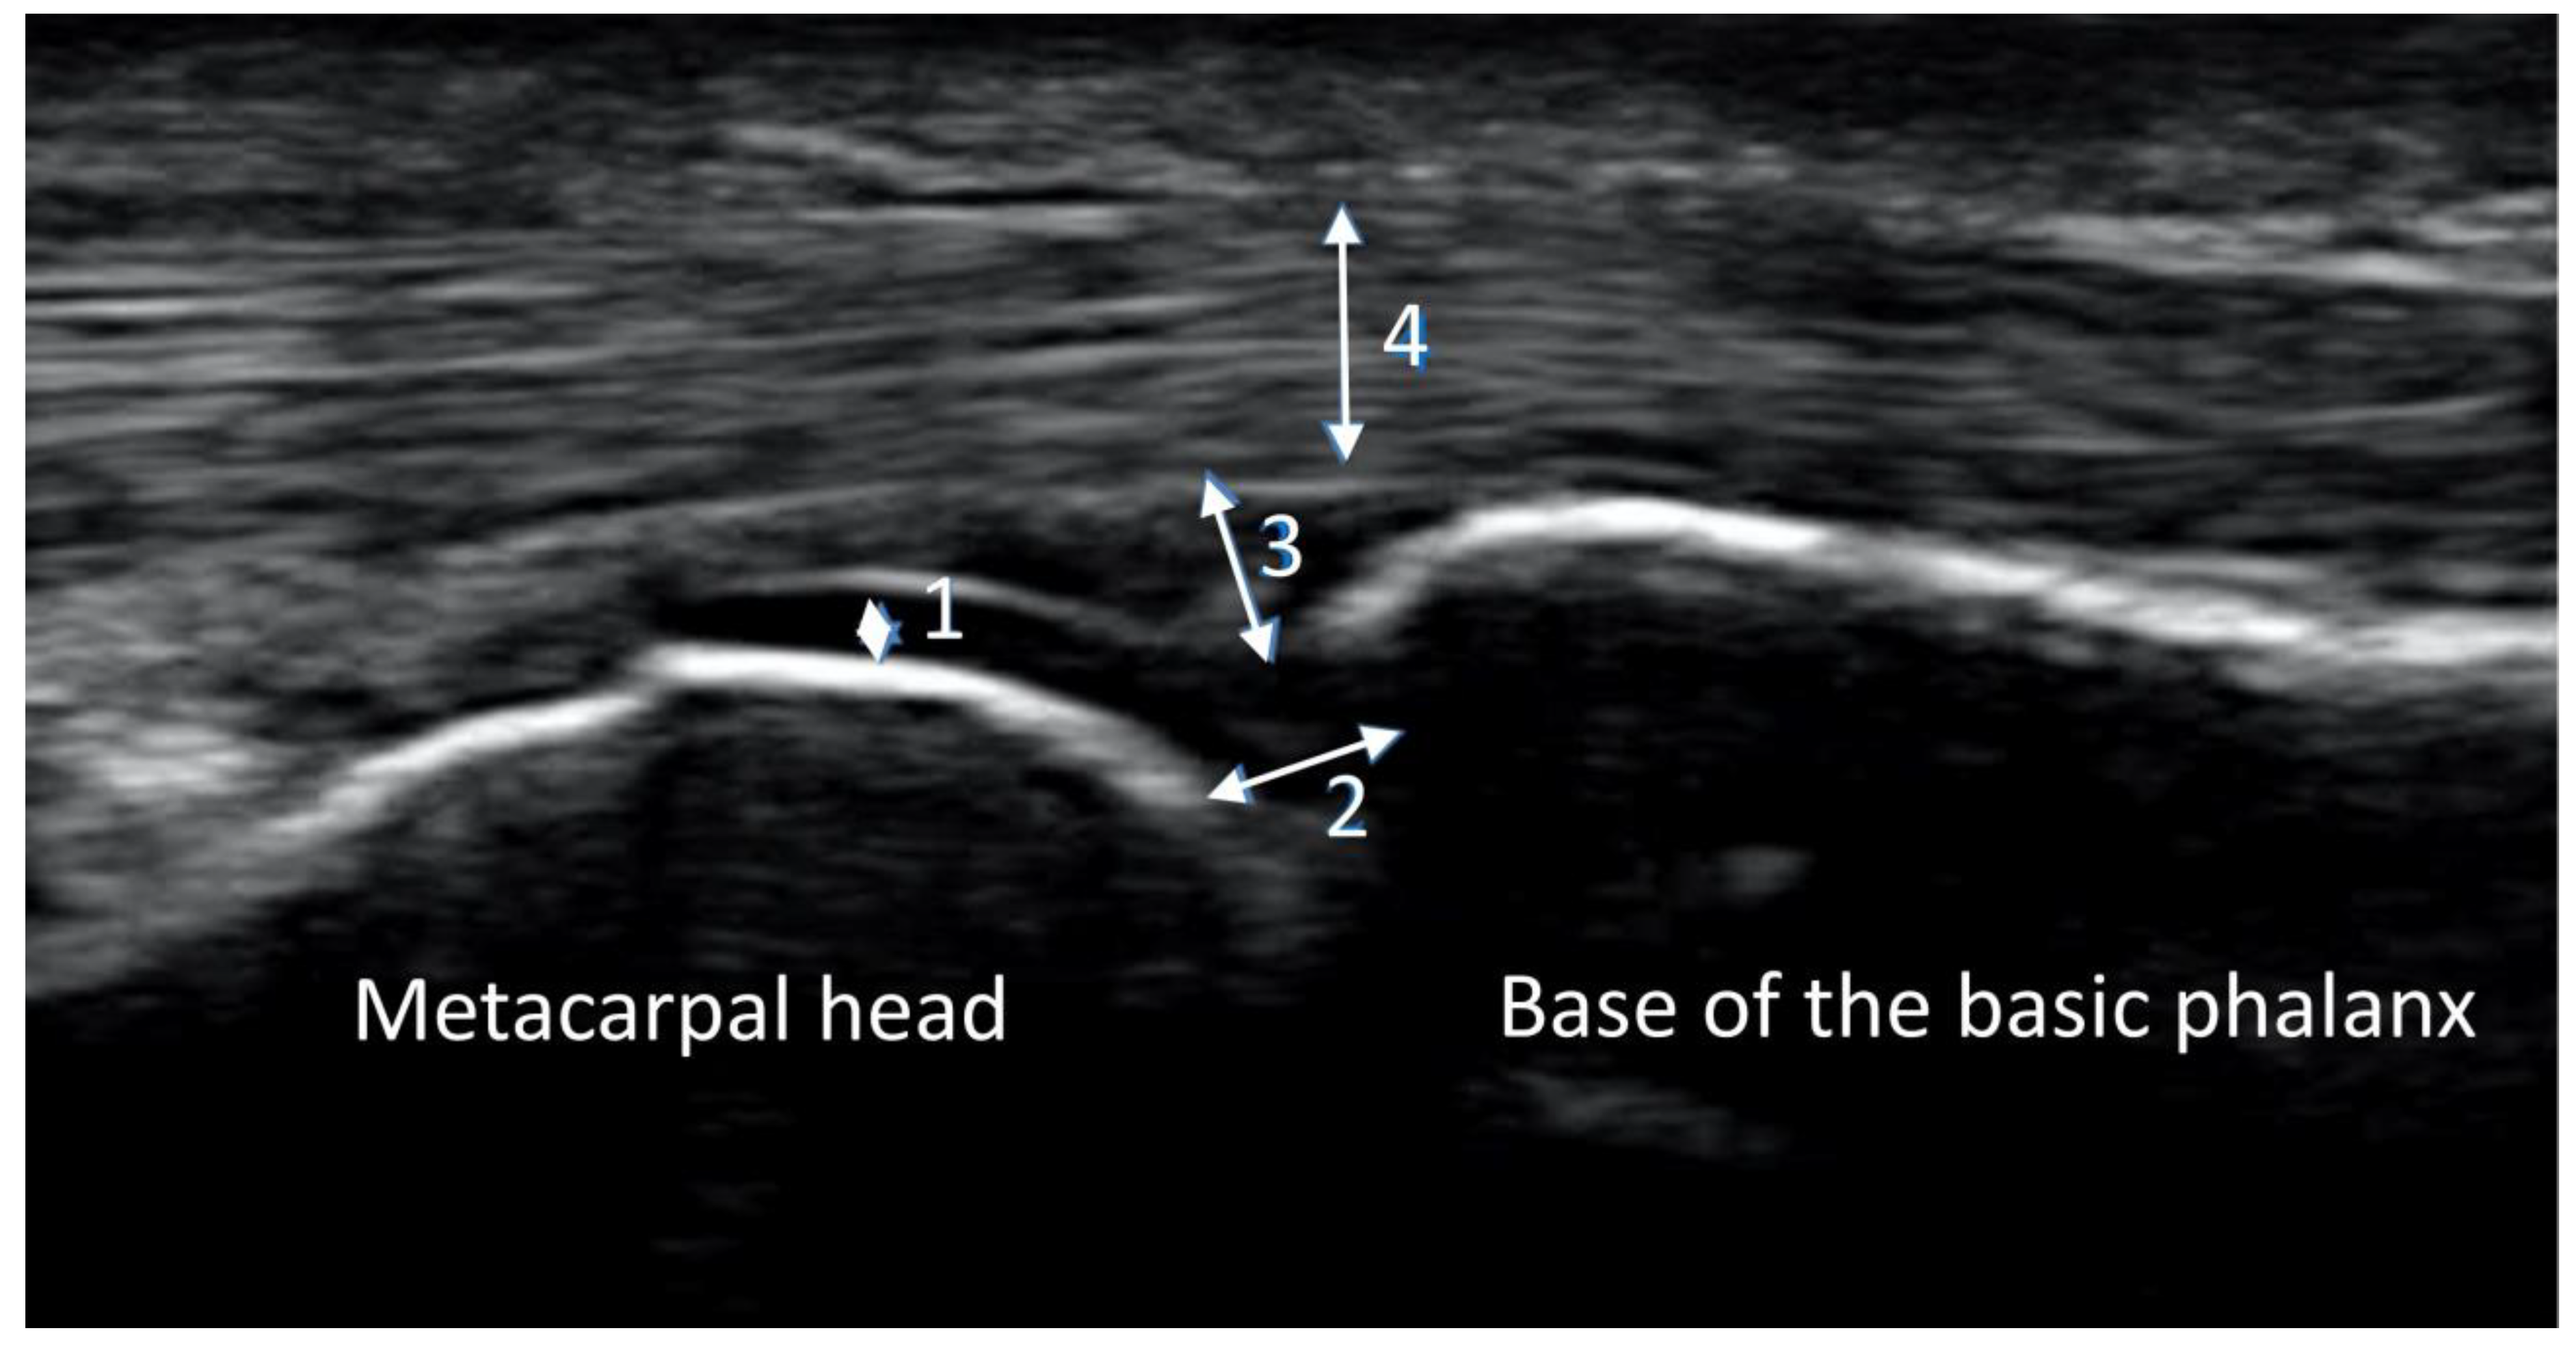

2.3. Ultrasound Imaging

2.4. Reading Procedures